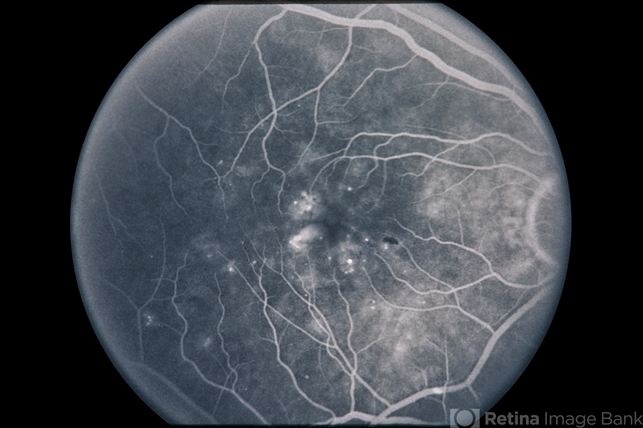

Diabetic Macular Edema

56-year-old patient with diabetic macular edema.